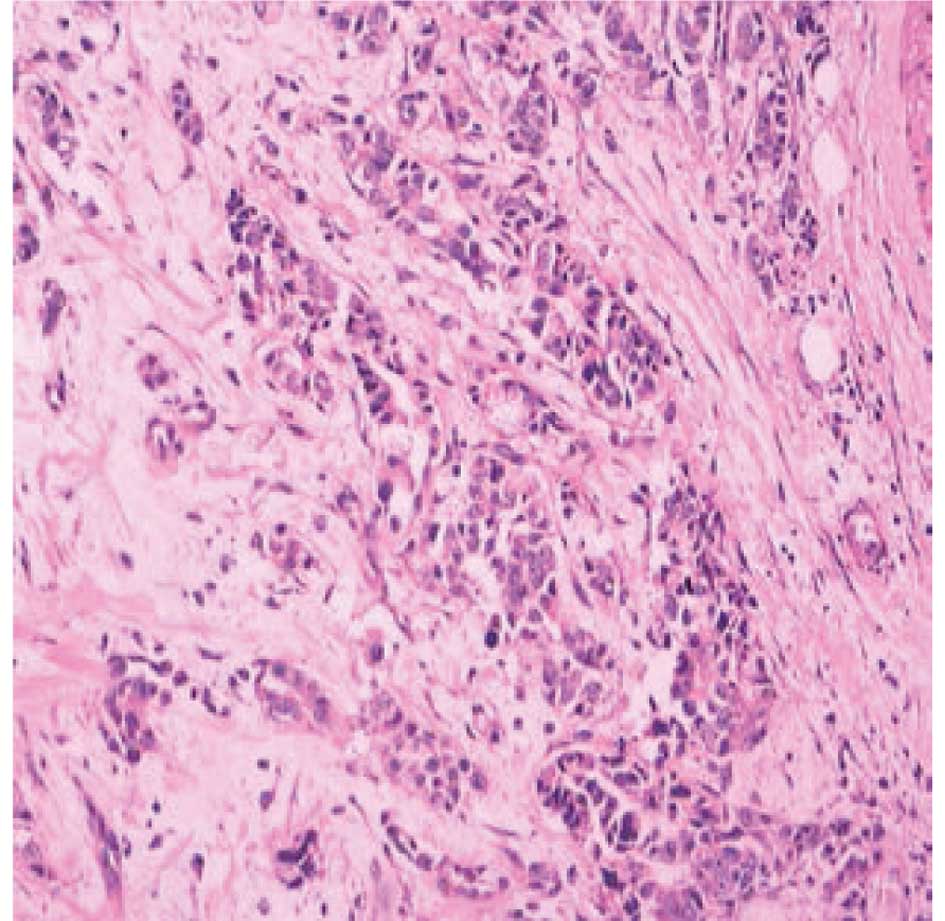

Carcinoma specimen analysis

The pathological specimen provided by the community

hospital showed an invasive ductal adenocarcinoma. According to an

immunohistochemical analysis, the cells were positive for the

estrogen receptor, progesterone receptor and p53 protein, and

negative for vascular endothelial growth factor and epidermal

growth factor receptor. The cells were markedly positive for C-erb

B2 (also known as HER-2/neu), and 30% of the tumor cells were

positive for the Ki-67 antigen (Fig.

1).